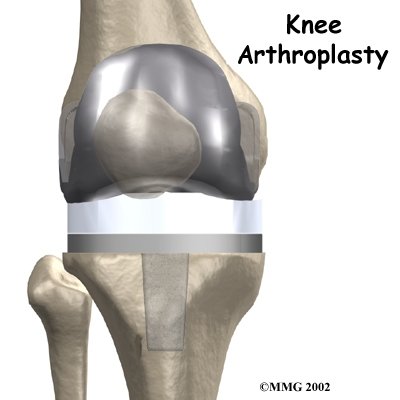

Each prosthesis is made up of three main parts.

The tibial component (bottom portion) replaces the top surface of the lower bone, the tibia. The femoral component (top portion) replaces the bottom surface of the upper bone (the femur) and the groove where the patella fits. The patellar component (kneecap portion) replaces the surface of the patella where it glides in the groove on the femur.

The femoral component is made of metal. The tibial component is usually made of two parts: a metal tray that is attached directly to the bone, and a plastic spacer that provides the slick surface. The plastic used is so tough and slick that you could ice skate on a sheet of it without damaging the material much. The patellar component is usually made of plastic as well. In some types of knee implants, the patellar component is made of a combination of metal and plastic.

The metal femoral component is then placed on the femur. In the uncemented prosthesis, the metal piece is held snugly onto the femur because the femur is tapered to accurately match the shape of the prosthesis. The metal component is pushed onto the end of the femur and held in place by friction. In the cemented variety, an epoxy cement is used to attach the metal prosthesis to the bone.

The metal tray that holds the plastic spacer is then attached to the top of the tibia. This metal tray is either cemented into place, or held with screws if the component is of the uncemented variety. The screws are primarily used to hold the tibial tray in place until bone grows into the porous coating. (The screws remain in place and are not removed.)

The plastic spacer is then attached to the metal tray of the tibial component. If this component should wear out while the rest of the artificial knee is sound, it can be replaced. The replacement procedure is called a retread.

The surgeon then sizes the patellar component andd puts it into place behind the patella. This piece is usually cemented in place.